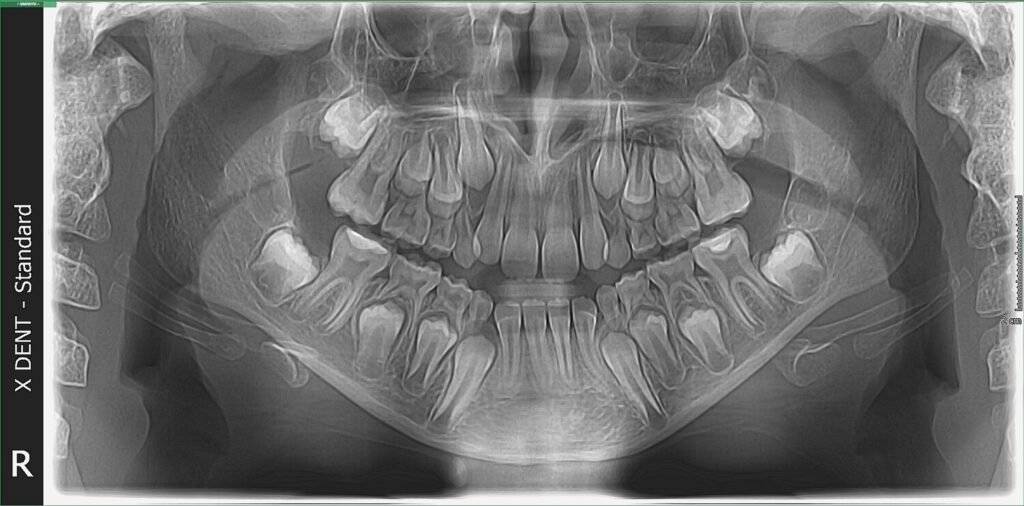

Dečiji ortopantomogram

Dečiji ortopantomogram, poznat i kao panoramski snimak zuba, predstavlja digitalni rendgenski snimak cele vilice, uključujući gornju i donju vilicu, sve zube, zubne zametke, kao i okolne koštane strukture. Ovaj snimak pruža širok i detaljan prikaz stanja u ustima deteta – čak i zuba koji još nisu iznikli.

Deciji ortopan